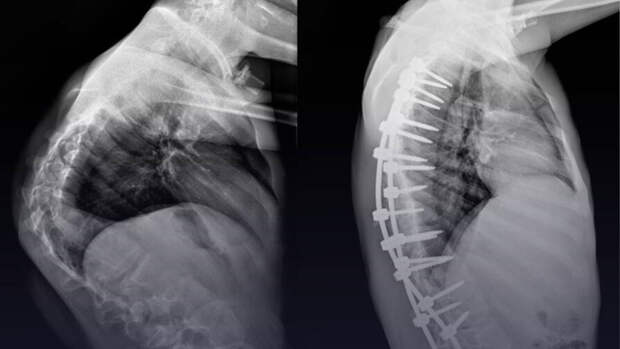

У мальчика диагностировали синдром Протея — редкое генетическое заболевание, которое провоцирует разрастание тканей и деформирует позвоночник. В медицинской практике описано лишь 200 подобных случаев. Было принято решение о сложнейшем хирургическом вмешательстве."Сложность заключалась в степени деформации. Из-за выраженных гипертрофических изменений позвонков пришлось прибегнуть к обширному частичному удалению некоторых костных структур, а также трех ребер, чтобы улучшить адаптацию органов грудной клетки после операции", — рассказал хирург-вертебролог отделения травматологии и ортопедии Андрей Пантелеев.

Патологию удалось скорректировать, врачи обещают, что после курса реабилитации качество жизни пациента улучшится.